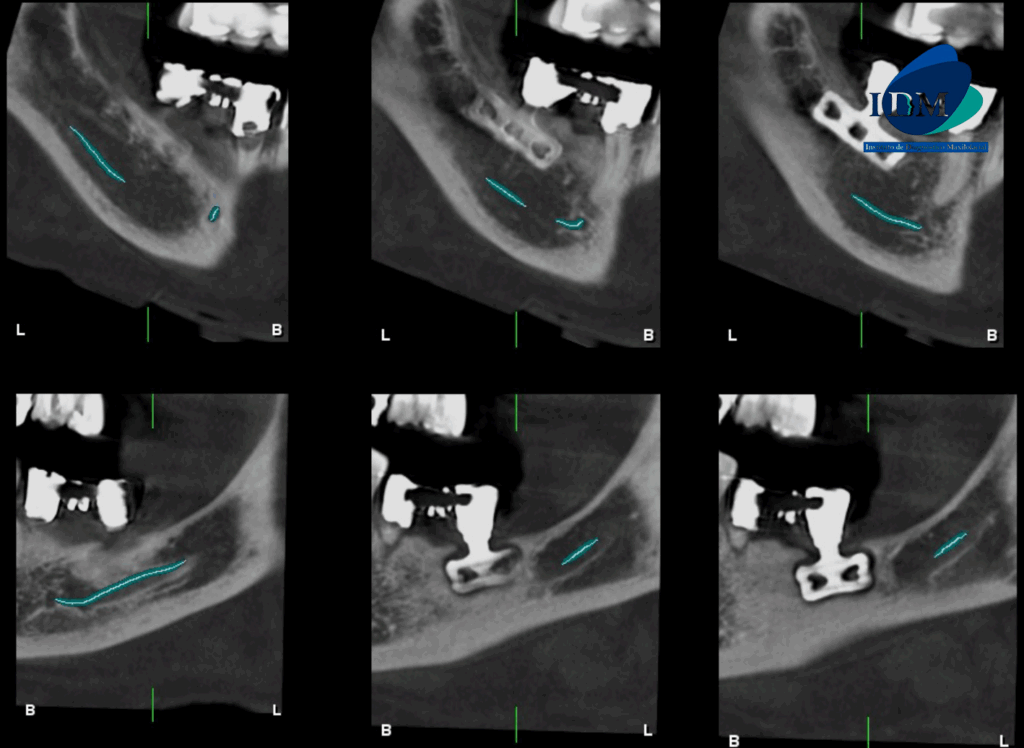

Al observar la tomografía computarizada de campo mediano se puede observar que los implantes en el maxilar inferior son efectivamente de tipo laminares o de lámina perforada, además se puede observar en vistas axiales la presencia de una imagen hipodensa circundante al implante de zona de pieza 36 (flecha azul), en vistas transaxiales y tangenciales se evidencian pérdida de continuidad de tejido óseo en tercio cervical; características que no presenta el implante en zona de pieza 46 (flecha amarilla- vista axial). Signos imagenológicos compatible con perimplantitis.

CORTES TRANSAXIALES